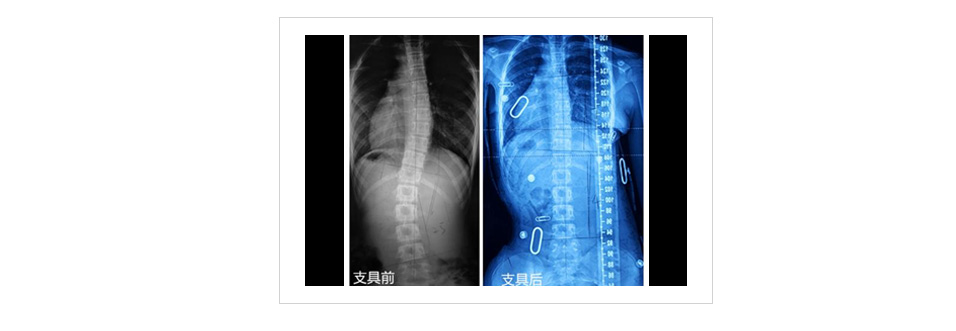

3D打印脊柱侧弯矫形器

脊柱侧弯矫形器是根据每个患者由于脊柱侧弯引起的身体变形,采用多组“三点力”从三维空间矫正畸形。矫正力是通过压力垫来实施的,压力垫的位置、形状、大小均可影响矫正效果。